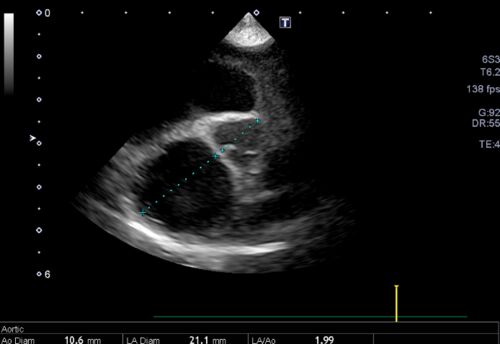

僧帽弁閉鎖不全症から肺水腫を経験したが長期生存したワンちゃん

「僧帽弁閉鎖不全症」とは、左心房と左心室の間にある僧帽弁が変性することで、逆流が生じてしまう状態のことを指します。 病態の進行に伴い、心臓はうっ血し更に悪化すると「肺水腫」という状態となり命の危険が生じます。 肺水腫とは、うっ血した心臓を原…